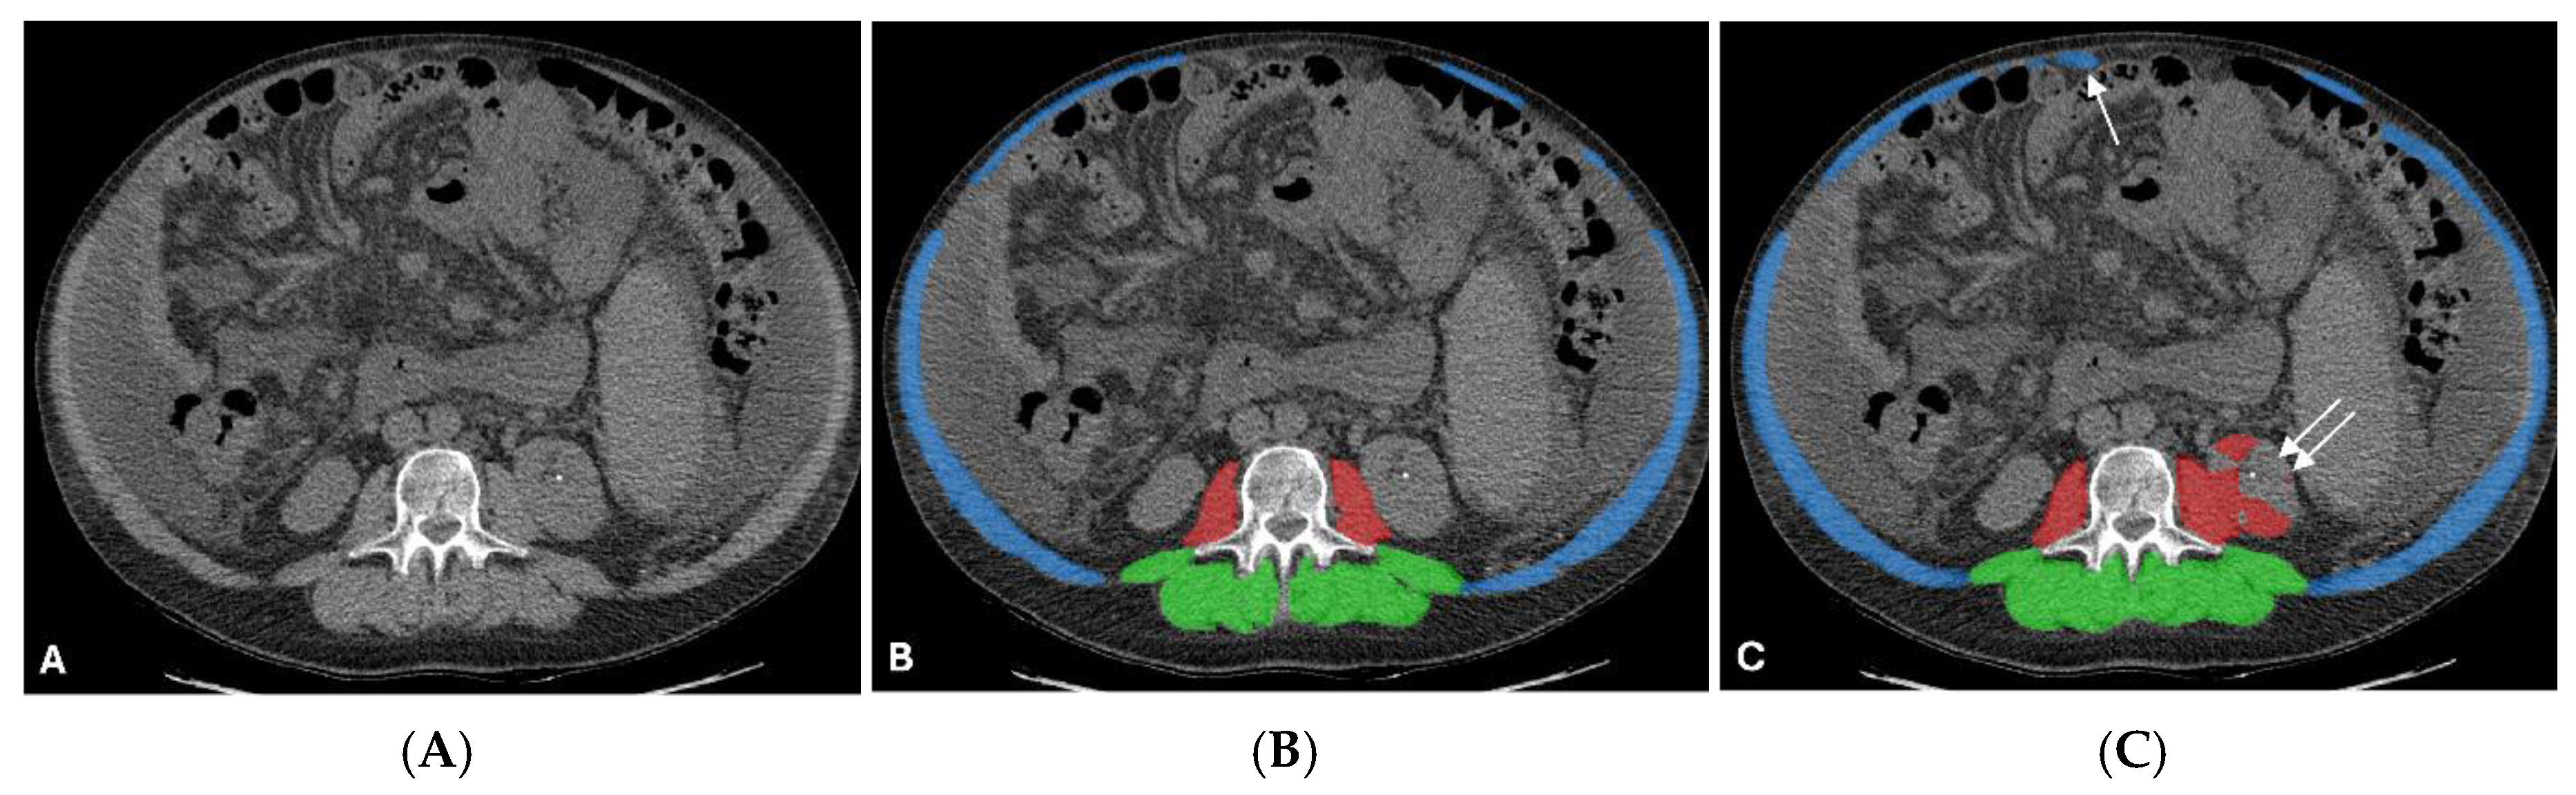

3.5. Qualitative Assessment and Error Analysis